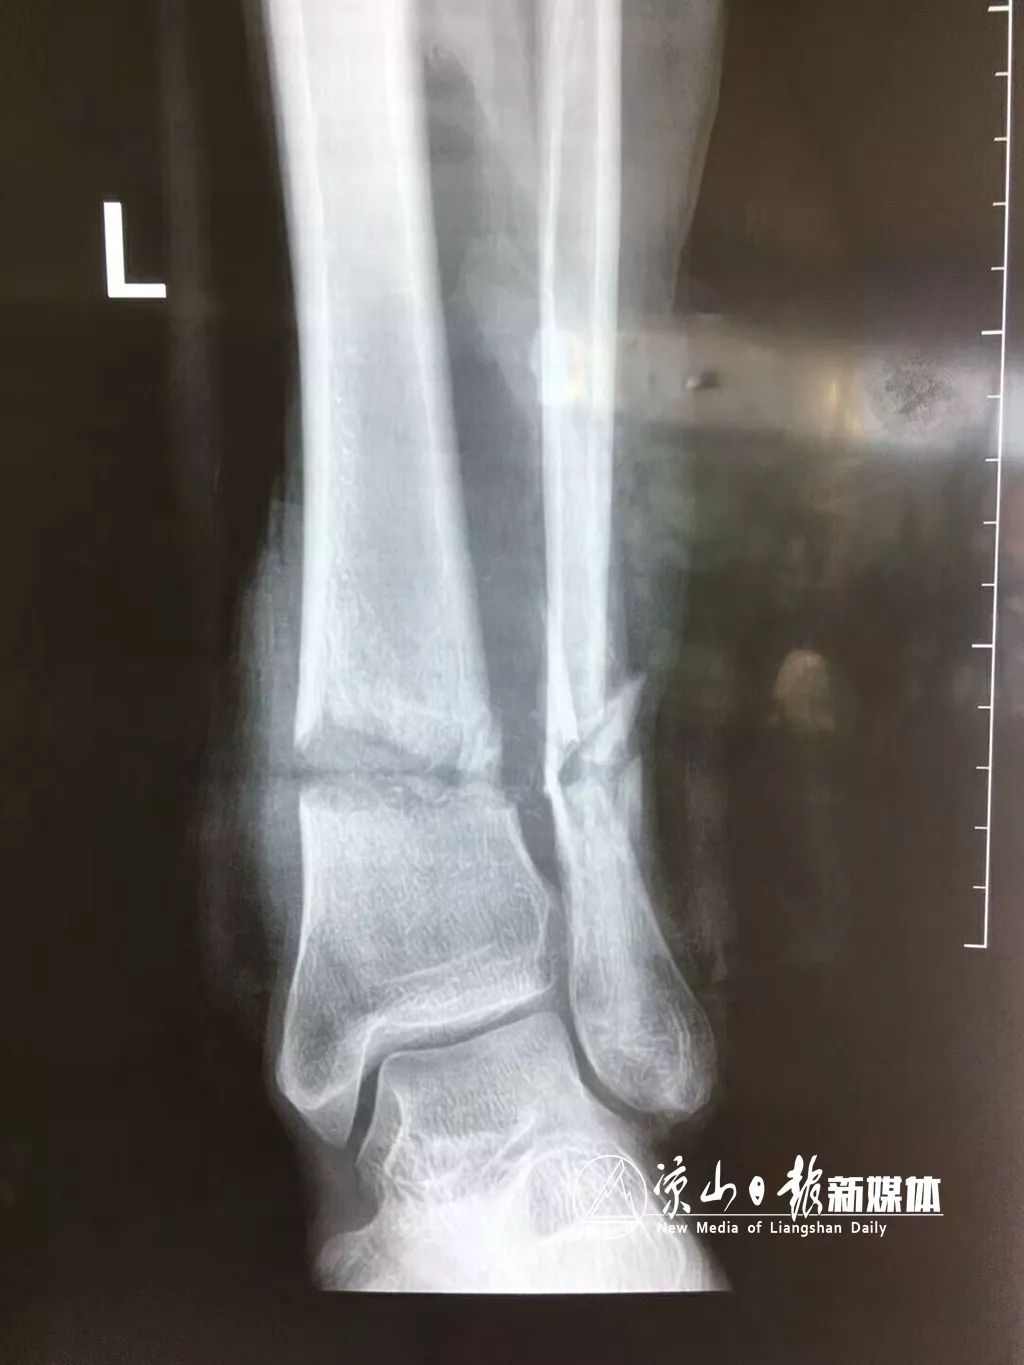

医生迅速进行相关检查后初步认定:病人左脚小腿下段环形离断,离断肢体仅靠外侧3cm少许表皮相连,创缘不齐,创周皮肤广泛撕脱,创区组织绞挫伤严重,左胫腓骨断端游离于创口外,血管肌腱(脚筋)、神经离断。创面有大约6×10厘米左右的皮肤组织复合缺损.创口处含有大量杂草、泥土等污染物。经院内张建国、花友坡、陈建中等专家会诊后,提出两种治疗方案:截肢术或断肢再植术(两种方案的优缺点:一、截肢术手术后伤口不易感染,恢复快,但将失去踝足;二、断肢再植术将保留踝足,但创口污染重,皮肤组织缺损多,手术复杂,吻合术后若肢体坏死,需二期截肢手术。因组织损伤严重,保肢过程中若出现毒素吸收导致肾功能衰竭时,依然需要截肢。)创伤手足外科科主任徐兵副主任医师建议患者及家属哪怕有一丝机会也绝不放弃。患者及家属经慎重考虑后决定先行保肢术。手术于当日上午10时许迅速而紧张的展开,在进行手术探查的过程当中发现:左胫前动脉缺失7厘米,造成动脉长度不够无法直接吻合,手术难度陡升,立即决定取大隐静脉移植桥接缺损的胫前动脉。经过7小时紧张施救后,完成了胫腓骨外固定、神经肌腱吻合、静脉吻合及动脉桥接吻合术,手术顺利,病员安全返病房。